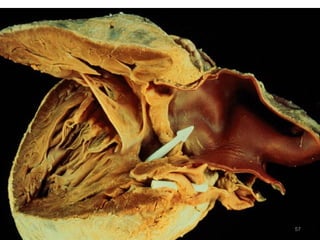

2.5   Hypoplastic Left Heart Syndrome

- Under development of Lt Side of the heart

- Atretic aortic or mitral orifice

- Non functional Lt ventricle

- Hypoplasia of ascending aorta

 Right ventricle supplies both pulm. &

systemic circulation